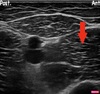

20.2 The structure labelled A shows (gastric ultrasound image shown)

a. Empty stomach

b. Full stomach with Solids

c. Full stomach with liquids and Air

d. Gall Bladder

e. Abdominal Aorta